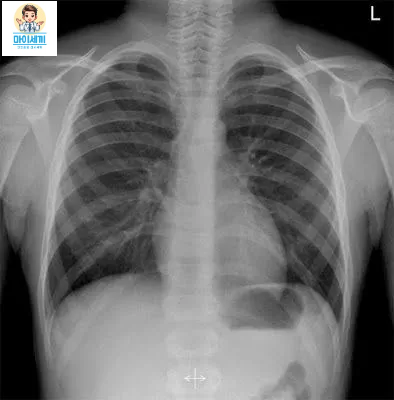

- 3. 흉부 X-레이: 폐 내 이상 소견을 확인하여 결핵 감염의 증거를 찾습니다. 결핵의 전형적인 X-레이 소견에는 폐에 나타나는 음영이나 기타 비정상적인 변화가 포함될 수 있습니다.

폐결핵 진단은 피부 반응 검사, 혈액 검사, 흉부 X-레이, 객담 검사 등을 통해 이루어집니다.